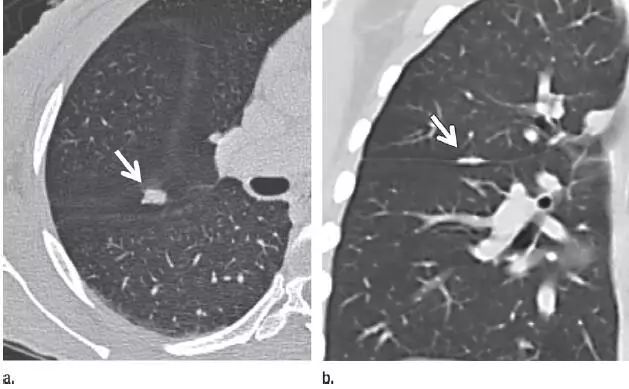

3、可疑部分实性结节

图 3(a)层厚 5 mm 的 CT 横断面图像,显示左肺下叶有明显的纯磨玻璃样结节(箭头)。(b)同一水平层厚 1 mm 的 CT 横断面图像,显示病变为一伴有囊性成分(箭头)的可疑部分实性结节。